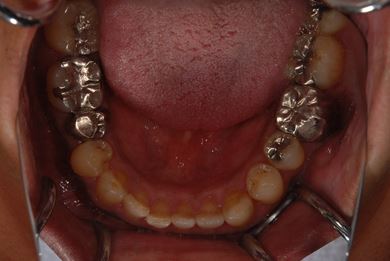

治療前

• 治療前